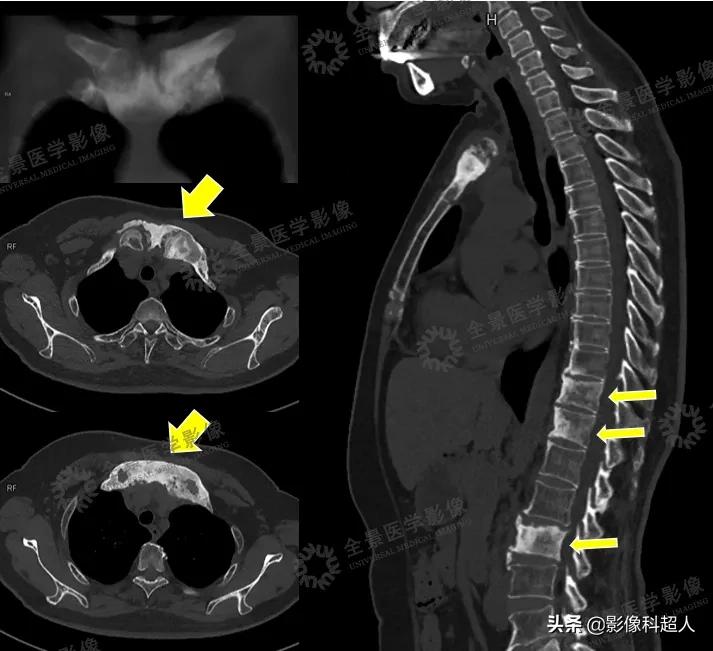

CT影像资料

多模态影像可见: • 双侧锁骨头、胸骨柄骨质肥厚,密度不均匀增高,T2WI呈不均匀低信号,DWI呈不均匀高信号,右侧胸锁关节FDG轻度摄取增高,SUVmax=2.5• 胸骨体上段见局灶性FDG摄取增高,SUVmax=3.7,DWI呈高信号,ADCmin=1.401,余序列未见明确显示,骨质密度未见明显异常• T11、T12、L3、L5椎体骨质密度不均匀增高,前角为著,T2WI呈高信号,DWI呈高信号,ADCmin=0.679,FDG摄取缺失

根据刘女士的影像检查表现,医生进一步询问刘女士相关临床症状,刘女士表示并没有明显的皮肤改变。 经过全面观察分析、会诊讨论后,根据典型的胸肋锁骨区、椎体前角受累等骨质硬化改变,医生考虑患者为 SAPHO综合征可能性大。